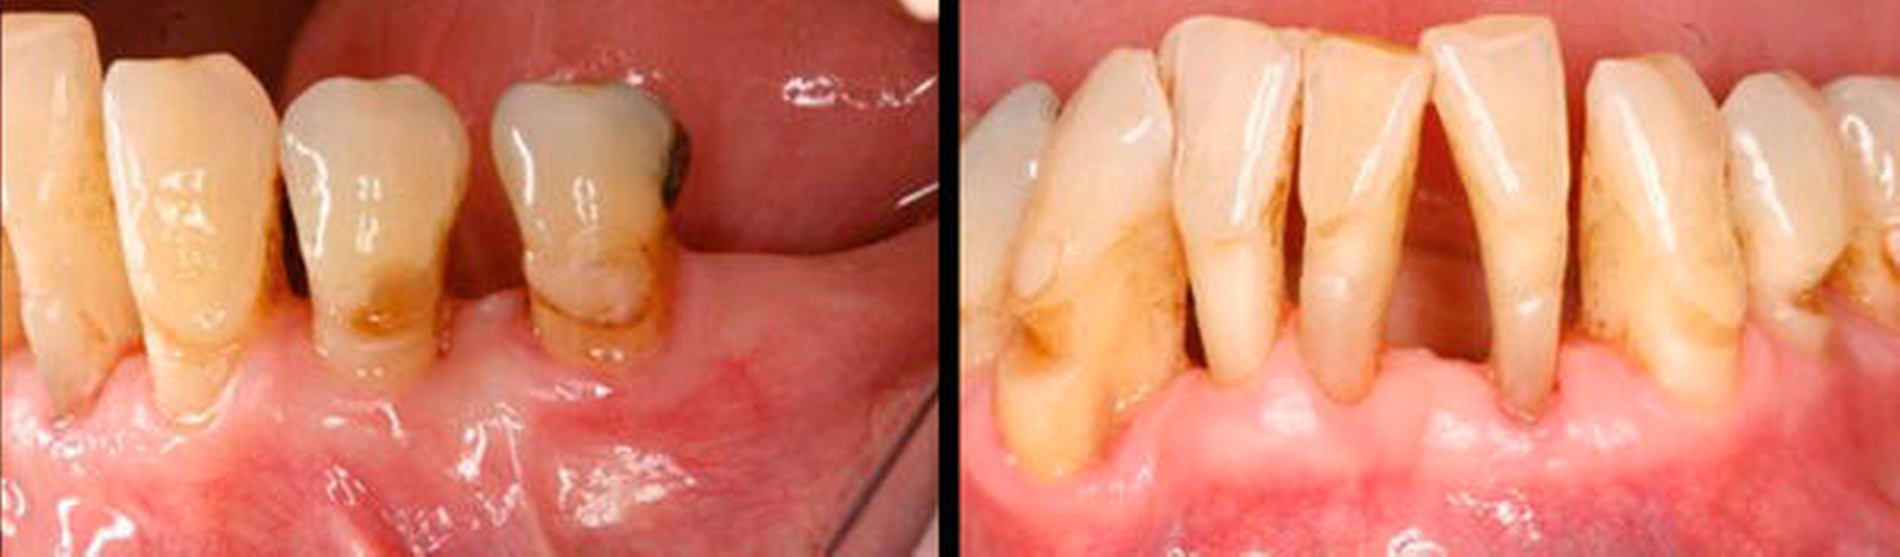

Schwere der Erkrankung

Der Grad der bei der Diagnose vorliegenden parodontalen Destruktion beschreibt die Schwere der Erkrankung, die sich nach der Größe des Attachmentverlusts oder des parodontalen Knochenabbaus bemisst. Der Schweregrad muss den Zahnverlust einbeziehen, der auf die Parodontitis zurückzuführen ist. Eine weitere Dimension der Schwere der Erkrankung ist die Komplexität der Behandlung. Faktoren wie zum Beispiel Sondierungstiefen, Art des Knochenabbaus (vertikal und/oder horizontal), Furkations-beteiligung, Zahnlockerung, Anzahl fehlender Zähne, Bisskollaps und erhöhte Komplexität der Behandlung müssen in die diagnostische Klassifizierung einbezogen werden. Ebenso sollte das Ausmaß der Erkrankung – definiert durch die Anzahl und Verteilung der Zähne mit erkennbarem parodontalen Abbau – in die Klassifizierung eingearbeitet werden.

Schwere:

Das Hauptziel ist, den Schweregrad und das Ausmaß der durch Parodontitis zerstörten und geschädigten Gewebe zu klassifizieren. Dies geschieht durch die Messung des CAL mittels klinischer Sondierung und des Knochenabbaus durch radiologische Untersuchung. Diese Messungen müssen die Anzahl der Zähne, deren Verlust auf eine Parodontitis zurückzuführen ist, beinhalten.

Komplexität:

Das sekundäre Ziel ist, die Komplexität zu bestimmen, die die Kontrolle der Erkrankung und das Management der langfristigen Funktion und Ästhetik der Dentition des Patienten erfordern.

Der Schwere-Wert basiert hauptsächlich auf dem interdentalen Attachmentverlust, der auf Parodontitis zurückzuführen ist, und dem marginalen Knochenabbau. Er wird bezogen auf den am stärksten betroffenen Zahn zugeordnet. Der Komplexitäts-Wert basiert auf der Komplexität der Behandlung des Falles. Er berücksichtigt Faktoren wie das Vorhandensein von ausgedehnten Sondierungstiefen, vertikalen Defekten, Furkationsbeteiligung, Zahnhypermobilität, Wanderungen und/oder Auffächerungen von Zähnen, Zahnverlust, Alveolarkammdefekten und Verlust der Kaufunktion.